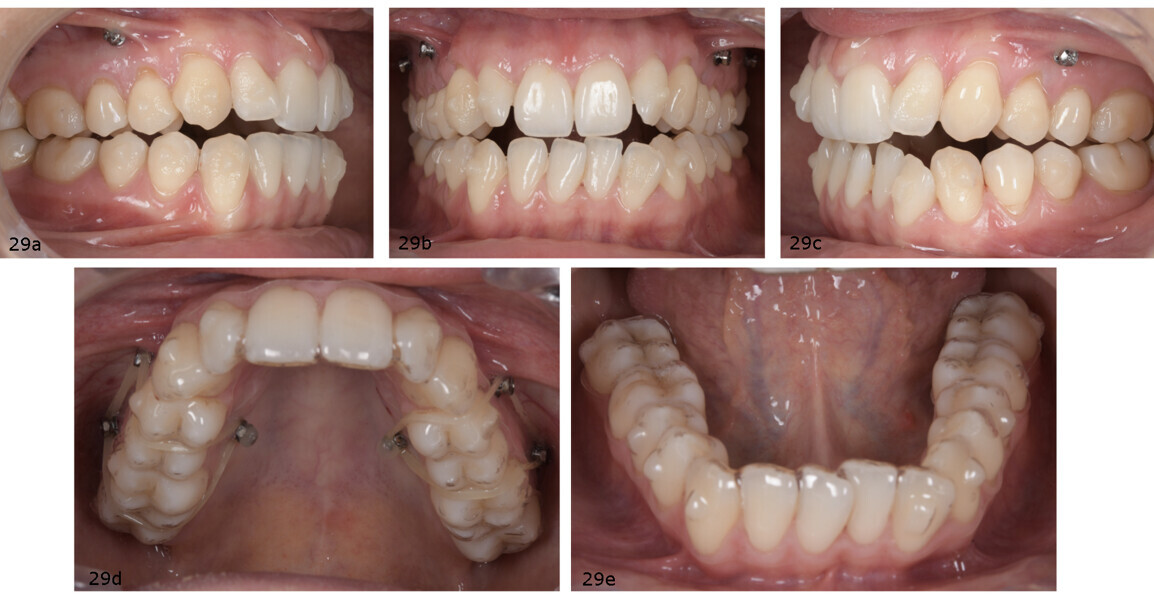

Since the required intrusion of the maxillary posterior teeth to enable mandibular auto-rotation exceeded 1 mm, interradicular mini-screws were indicated to enhance force application and ensure controlled vertical movement (Fig. 28). At the first clinical appointment, the attachments were bonded according to the digital set-up. A total of six mini-screws were placed in the maxilla: four buccally between the first and second premolars and two palatally between the first molar and second premolar. The patient was instructed to wear 5⁄16 in., 8 oz elastics bilaterally over the aligners and attached to the mini-screws in order to facilitate posterior intrusion (Fig. 29).

The active orthodontic treatment was carried out with 60 maxillary and mandibular aligners, delivered in phases: 30 aligner pairs or the initial phase, 18 aligners for the first refinement and 12 aligner pairs for the second refinement. In the final phase of treatment, 3⁄16 in., 4.5 oz intermaxillary elastics were prescribed to improve the Class II dental relationship and enhance final intercuspation. The total treatment time was 18 months, including periods where the patient wore Essix-type retainers between refinement phases.